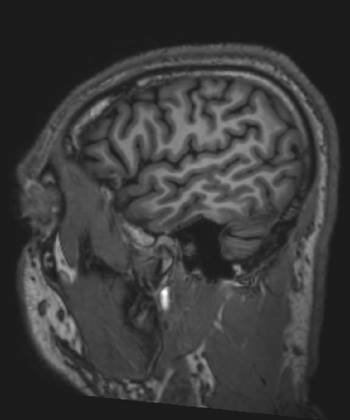

Formación de la imagen en múltiples tecnologías (Resonancia Nuclear Magnética)

El doctor Raymond Damadian demostró que la resonancia magnética podía ser usada para detectar enfermedades porque distintos tipos de tejidos emiten señales que varían en su duración, en respuesta al campo magnético.

El investigador Paul Lauterbur desarrolló la técnica para generar las primeras imágenes en resonancia magnética en 2 y 3 dimensiones